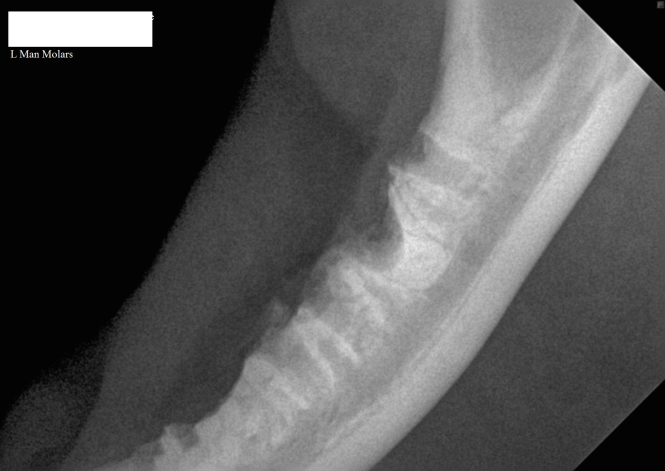

3.	Intra-oral radiograph of the left mandible of a cat with a retained mesial root of the molar tooth.

3.      Intra-oral radiograph of the left mandible of a cat with a retained mesial root of the molar tooth

Incomplete extraction of teeth has been a cause of poor response to treatment and so pre and post extraction dental radiographs are exceedingly important. Extraction technique, with focus on minimizing surgical trauma, has a significant role in achieving short term comfort and post operative patient recovery.